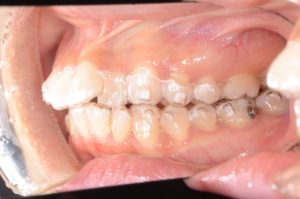

【インビザラインにて動的治療スタート】

約2年6ヵ月、インビザラインによる非抜歯での動的治療。